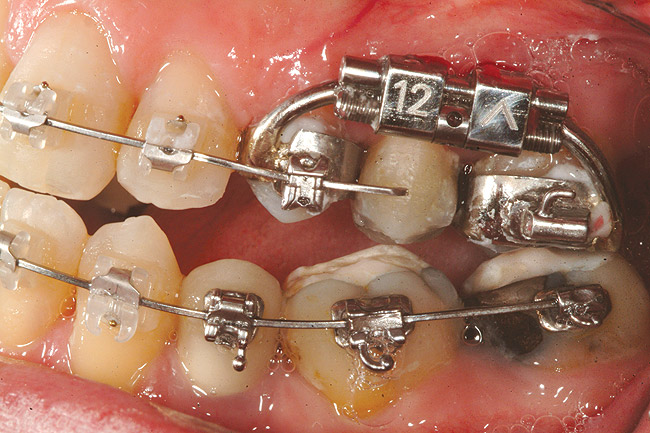

Fig 18 (through Fig 21). Note lack of alveolar development from congenitally missing Nos. 24 and 25. Surgical procedures after 5 months of orthodontic alignment included single-tooth osteotomies Nos. 6 to 11 and Nos. 21 to 28 and buccal corticotomies on all other teeth. Anchorage plate was stabilized to piriform rim.

Figure 18

Fig 20. Note lack of alveolar development from congenitally missing Nos. 24 and 25. Surgical procedures after 5 months of orthodontic alignment included single-tooth osteotomies Nos. 6 to 11 and Nos. 21 to 28 and buccal corticotomies on all other teeth. Anchorage plate was stabilized to piriform rim.

Figure 20

Fig 21 (and Fig 20). There is significant lateral dentoalveolar expansion of arches and alveoloskeletal correction in maxillary and mandibular anterior regions. Alveolar bone volume was increased in lower anterior to create optimal implant sites and establish ideal interincisal function and stability.